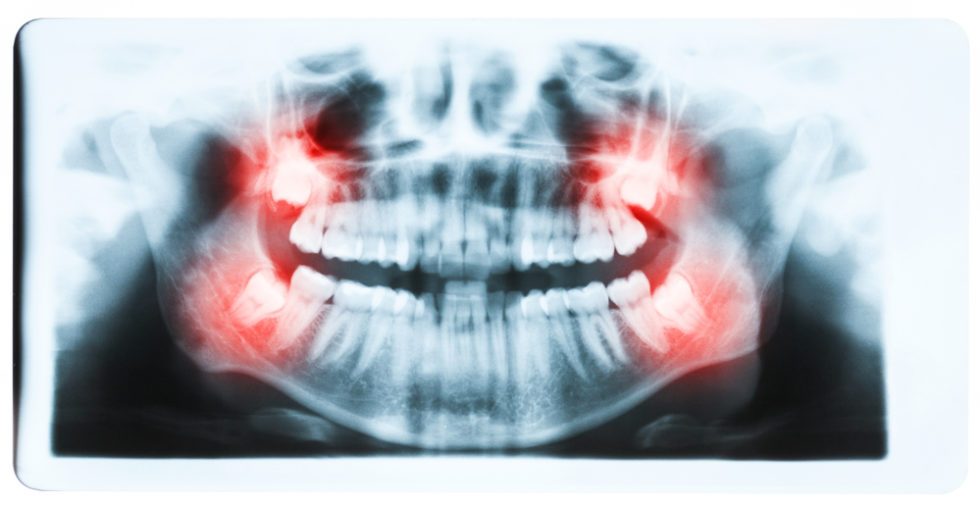

How to Tell Between an Erupting and Impacted Wisdom Tooth 9 Steps

Wisdom Tooth Impaction in Ventura, CA Pacific Oral Surgery What Does Wisdom Tooth Eruption Feel Like Wisdom teeth can cause problems if. Sometimes a wisdom tooth becomes stuck below the surface of your gums and. While many people will have their third molars erupt without any. vertical impaction is when your wisdom tooth is in the correct position for eruption, but it’s still trapped beneath your gums. wisdom teeth are the last of your. What Does Wisdom Tooth Eruption Feel Like.

How to Tell Between an Erupting and Impacted Wisdom Tooth 9 Steps What Does Wisdom Tooth Eruption Feel Like some signs your wisdom teeth are erupting include tender and swollen gums, headaches, and jaw pain. to tell the difference between an. vertical impaction is when your wisdom tooth is in the correct position for eruption, but it’s still trapped beneath your gums. A toothache is often the first sign of wisdom teeth coming in. wisdom. What Does Wisdom Tooth Eruption Feel Like.